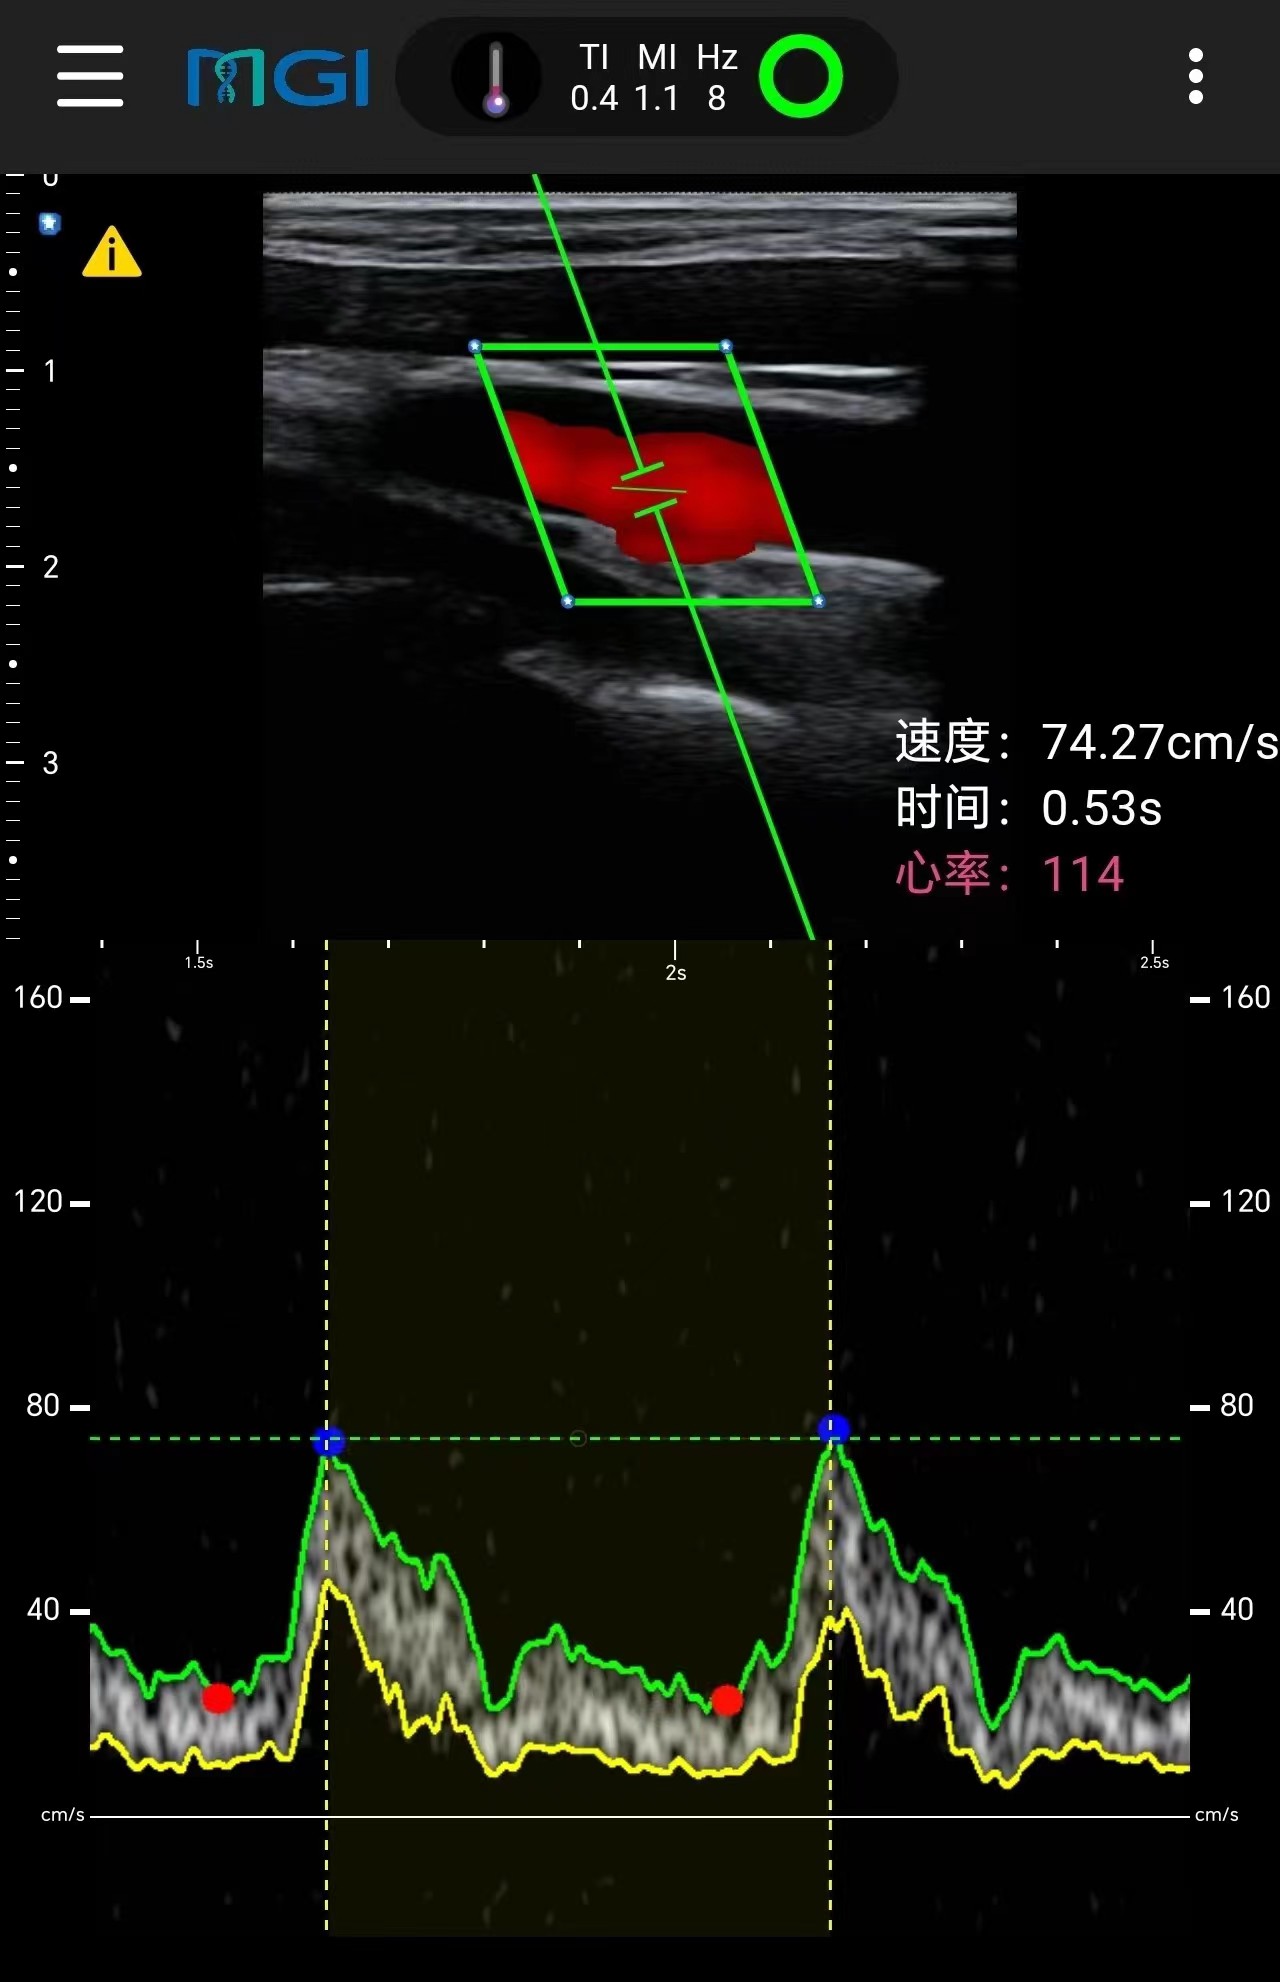

在珠峰顶实时获取的颈动脉超声扫查图像。

当日10时28分,华大集团联合创始人、董事长汪建带领华大登山队,从北坡成功登顶珠穆朗玛峰。华大智造的无线掌上超声,在珠峰峰顶实时获取登顶队员的颈动脉超声扫查图像,这成为全球首张诞生于世界之巅的超声图。

此外,在海拔8300米的营地,华大登山队员还使用无线掌上超声设备,完成了与北京、四川阿坝、广东深圳连线,成功实现会诊,并对登山队员进行了颈动脉实时超声扫查,以探索颈动脉血流动力学在极端高海拔地区的影响。